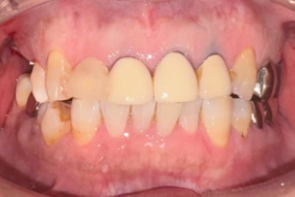

年間1,000症例以上の 「世界レベル」オペ実施

最安で税込99,800円~の低価格を実現